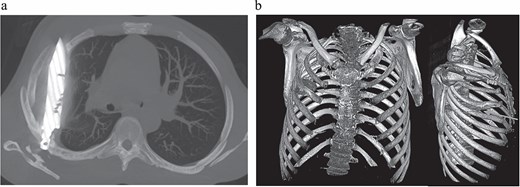

Initial imaging with a lateral chest radiograph demonstrated a retained metallic object in the mid-thorax, with surrounding opacification likely representing a resolving or chronic loculated hematoma or post-traumatic fibrosis, a sequela of the patient's stab wound (Fig. 2). Subsequent computed tomography (CT) imaging (Fig. 3a and b) revealed a retained foreign metallic object traversing the right chest. The entry point was identified through the right scapula, between the 5th and 6th posterior intercostal spaces, with the tip extending to the 3rd and 4th anterior intercostal spaces. CT also demonstrated healed fractures of the right scapula, 5th and 6th ribs posteriorly, and the 3rd rib anteriorly. An elliptical area of consolidation with central hypodensity was observed, further supporting the interpretation of a resolved or chronic loculated hematoma. The remainder of the lung parenchyma appeared unremarkable.

(a) CT chest maximum intensity projection (MIP) demonstrating a retained metallic foreign body (knife) traversing the right chest, with associated healed fractures. (b) 3D reconstructed CT chest image demonstrating the retained knife and associated skeletal injuries.